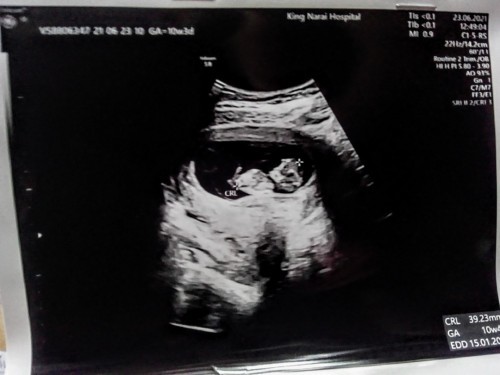

กินอะไรเพิ่มน้ำหนักลูกดีคะ รู้สึกว่าตัวลูกน้อยเกินไป #ขอคำแนะนำหน่อยค่ะ #ขอบคุณล่วงหน้านะคะ